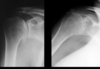

What are the findings & dx of this case?

- Non-uniform loss of inferior GH joint

- Inferior Osteophytes at inferior GH

- Concretion type of calcifications in axillary pouch

- OA (or DJD) of GH joint with secondary synovial osteochondrometaplasia